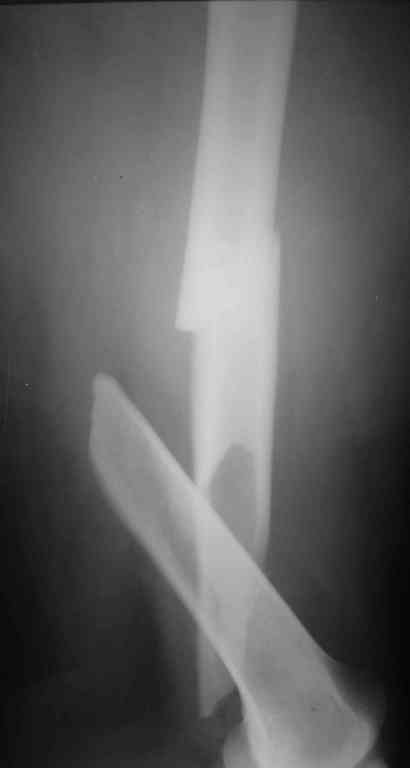

К сожалению никакой информации кроме рентгенограммы

одного из бедер, и то в одной проекции не представлено. Но и исходя из представленного снимка я бы предпочёл длинную гамму(производитель в принципе значения не имеет, если это не подпольная организация).

По представленному снимку выполнял бы антеградное введение стержня, длинна дистального отломка позволяет. Только блокирование более чем в одной плоскости.